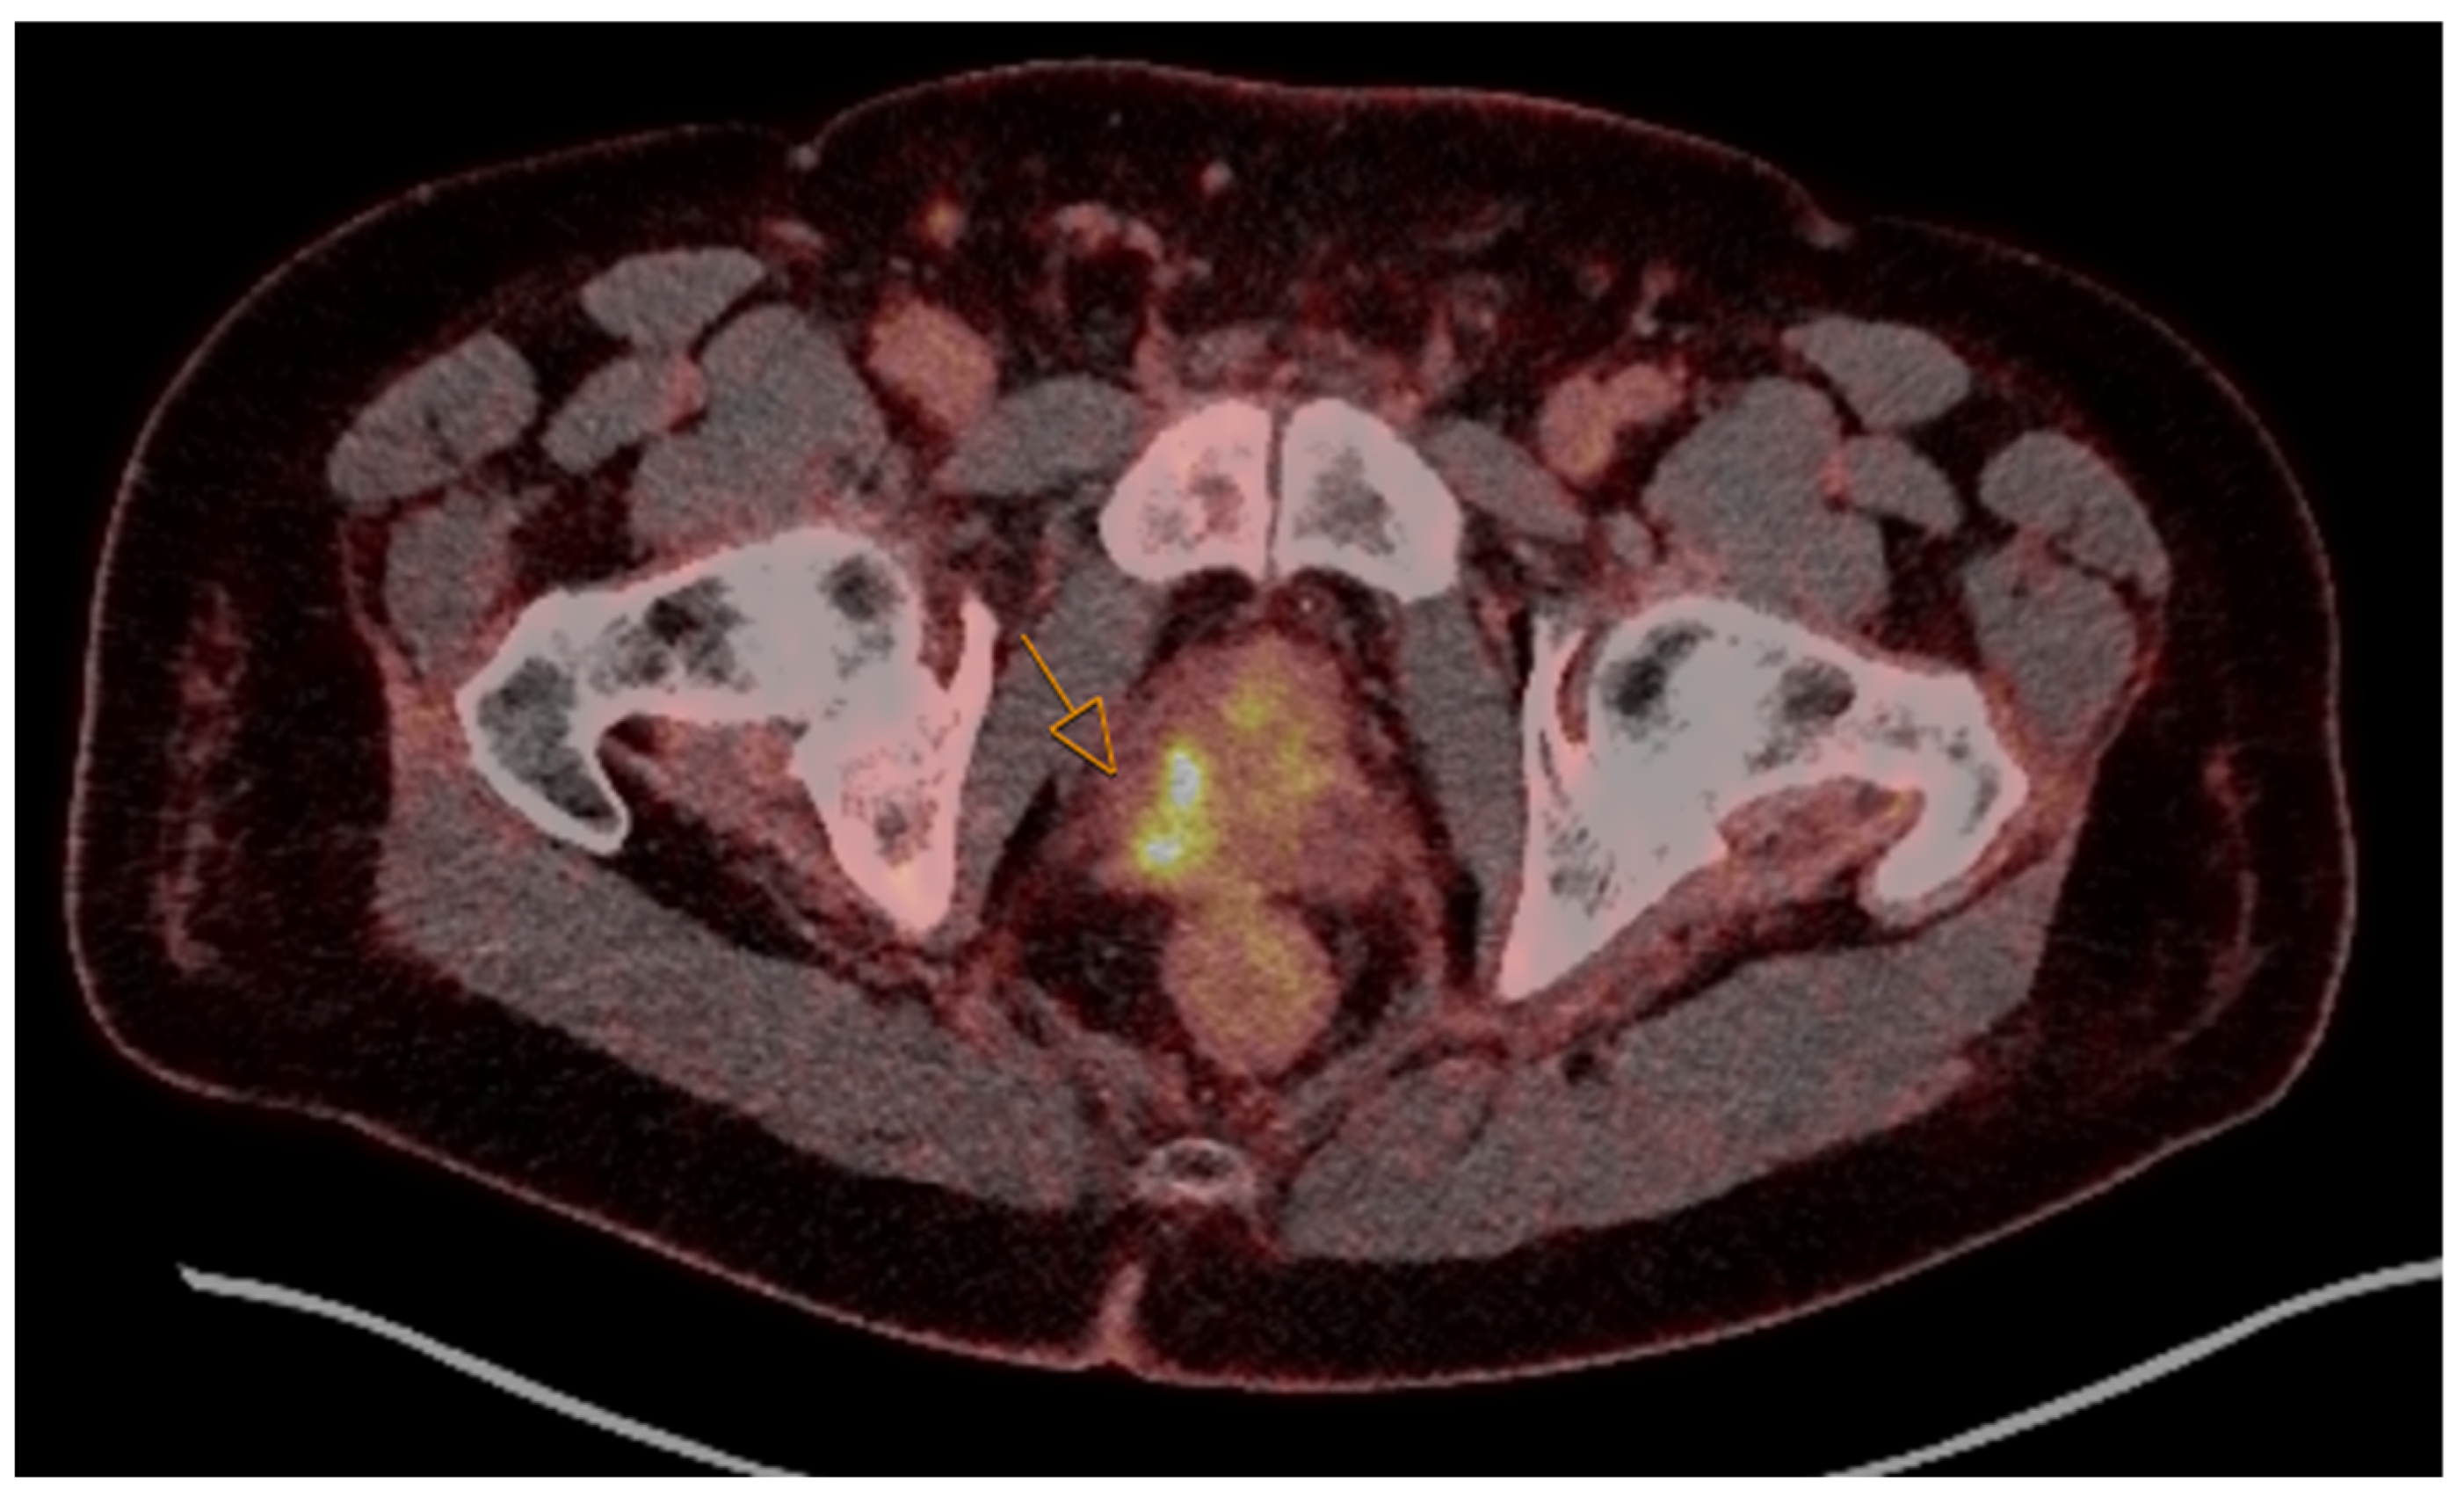

3. MRI, PSMA PET/CT, and Ultrasound in Prostate Cancer Imaging and Specific AI Applications